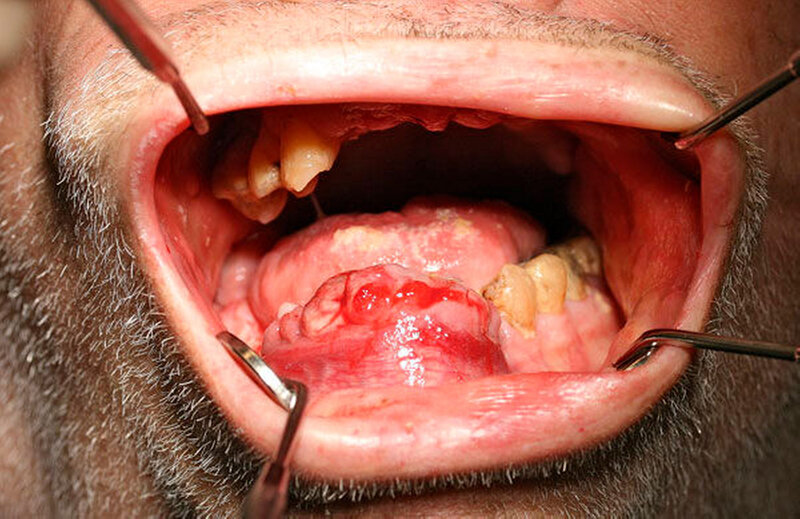

Intraoral fand sich eine ausgedehnte, ulzeröse, druckdolente, erhabene Raumforderung regio 44–33 mit Übergang ins Vestibulum und in den Mundboden (Abbildung 2). Die Zunge und die Unterlippe waren frei. Zudem zeigte sich eine profuse Blutung aus den Extraktionsalveolen regio 31 und 41. Die Zähne 32, 33, 42 und 43 standen in der tumorösen Raumforderung und zeigten eine Lockerung dritten Grades. Die Sensibilitäts- und Perkussionsproben dieser Zähne waren negativ. Daneben fand sich eine starke Blutungsneigung auf Sondierung.